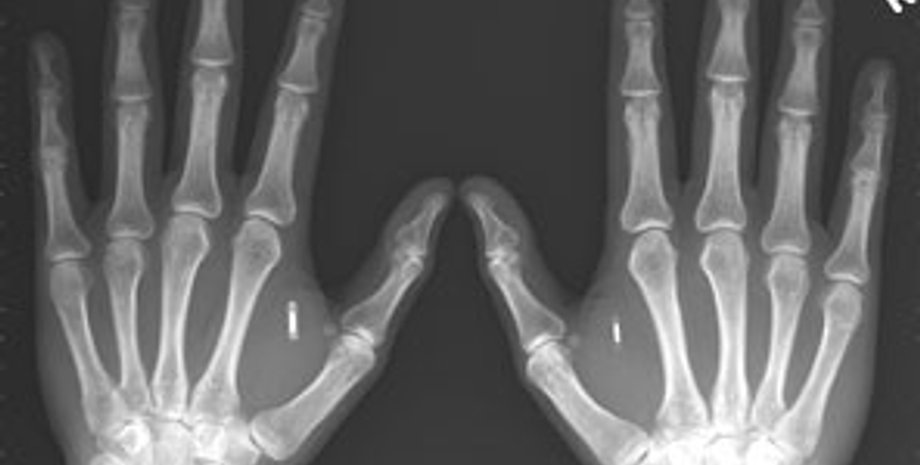

Ученым из Технологического института штата Джорджия удалось создать искусственные кости, которые обладают важным качеством: они способны «срастаться» с иными тканями организма, такими как сухожилия и мускулы.

Новые кости обещают стать причиной небольшой революции в сфере травматологии. Они созданы посредством генной инженерии: фактически, полимерный материал был искусственно совмещен с клетками кожи. Лабораторные опыты показали, что эта методика позволяет достичь успеха. В ближайшее время новая технология будет проходить испытания на животных.

Ранее Пентагон официально анонсировал создание нового Института регенеративной медицины при Министерстве обороны США, который должен будет заняться изучением технологии применения и получения стволовых клеток, а также созданием комплексных систем для восстановления кожи, мышечных и костных тканей. В отдаленной перспективе планируется воссоздавать и целые фрагменты тела - пальцы, нос, уши и т. д.

Как сообщает Сybersecurity.ru, для осуществления научной деятельности новый институт получил 250 млн. долларов на предстоящие 5 лет. В Минобороны США также сообщили, что в проекте принимают участие и негосударственные исследовательские лаборатории, три университета и ряд частных инвесторов, которые намерены коммерциализировать технологию выращивания новых органов.

Специалисты отмечают, что за последние три года многие научные заведения по всему миру уже активно регенерируют кожные ткани животных и человека, однако во всех случаях этот процесс идет с применением так называемых внеклеточных матриц. В новом же институте планируется выращивание тканей с нуля, только при помощи генного материала.